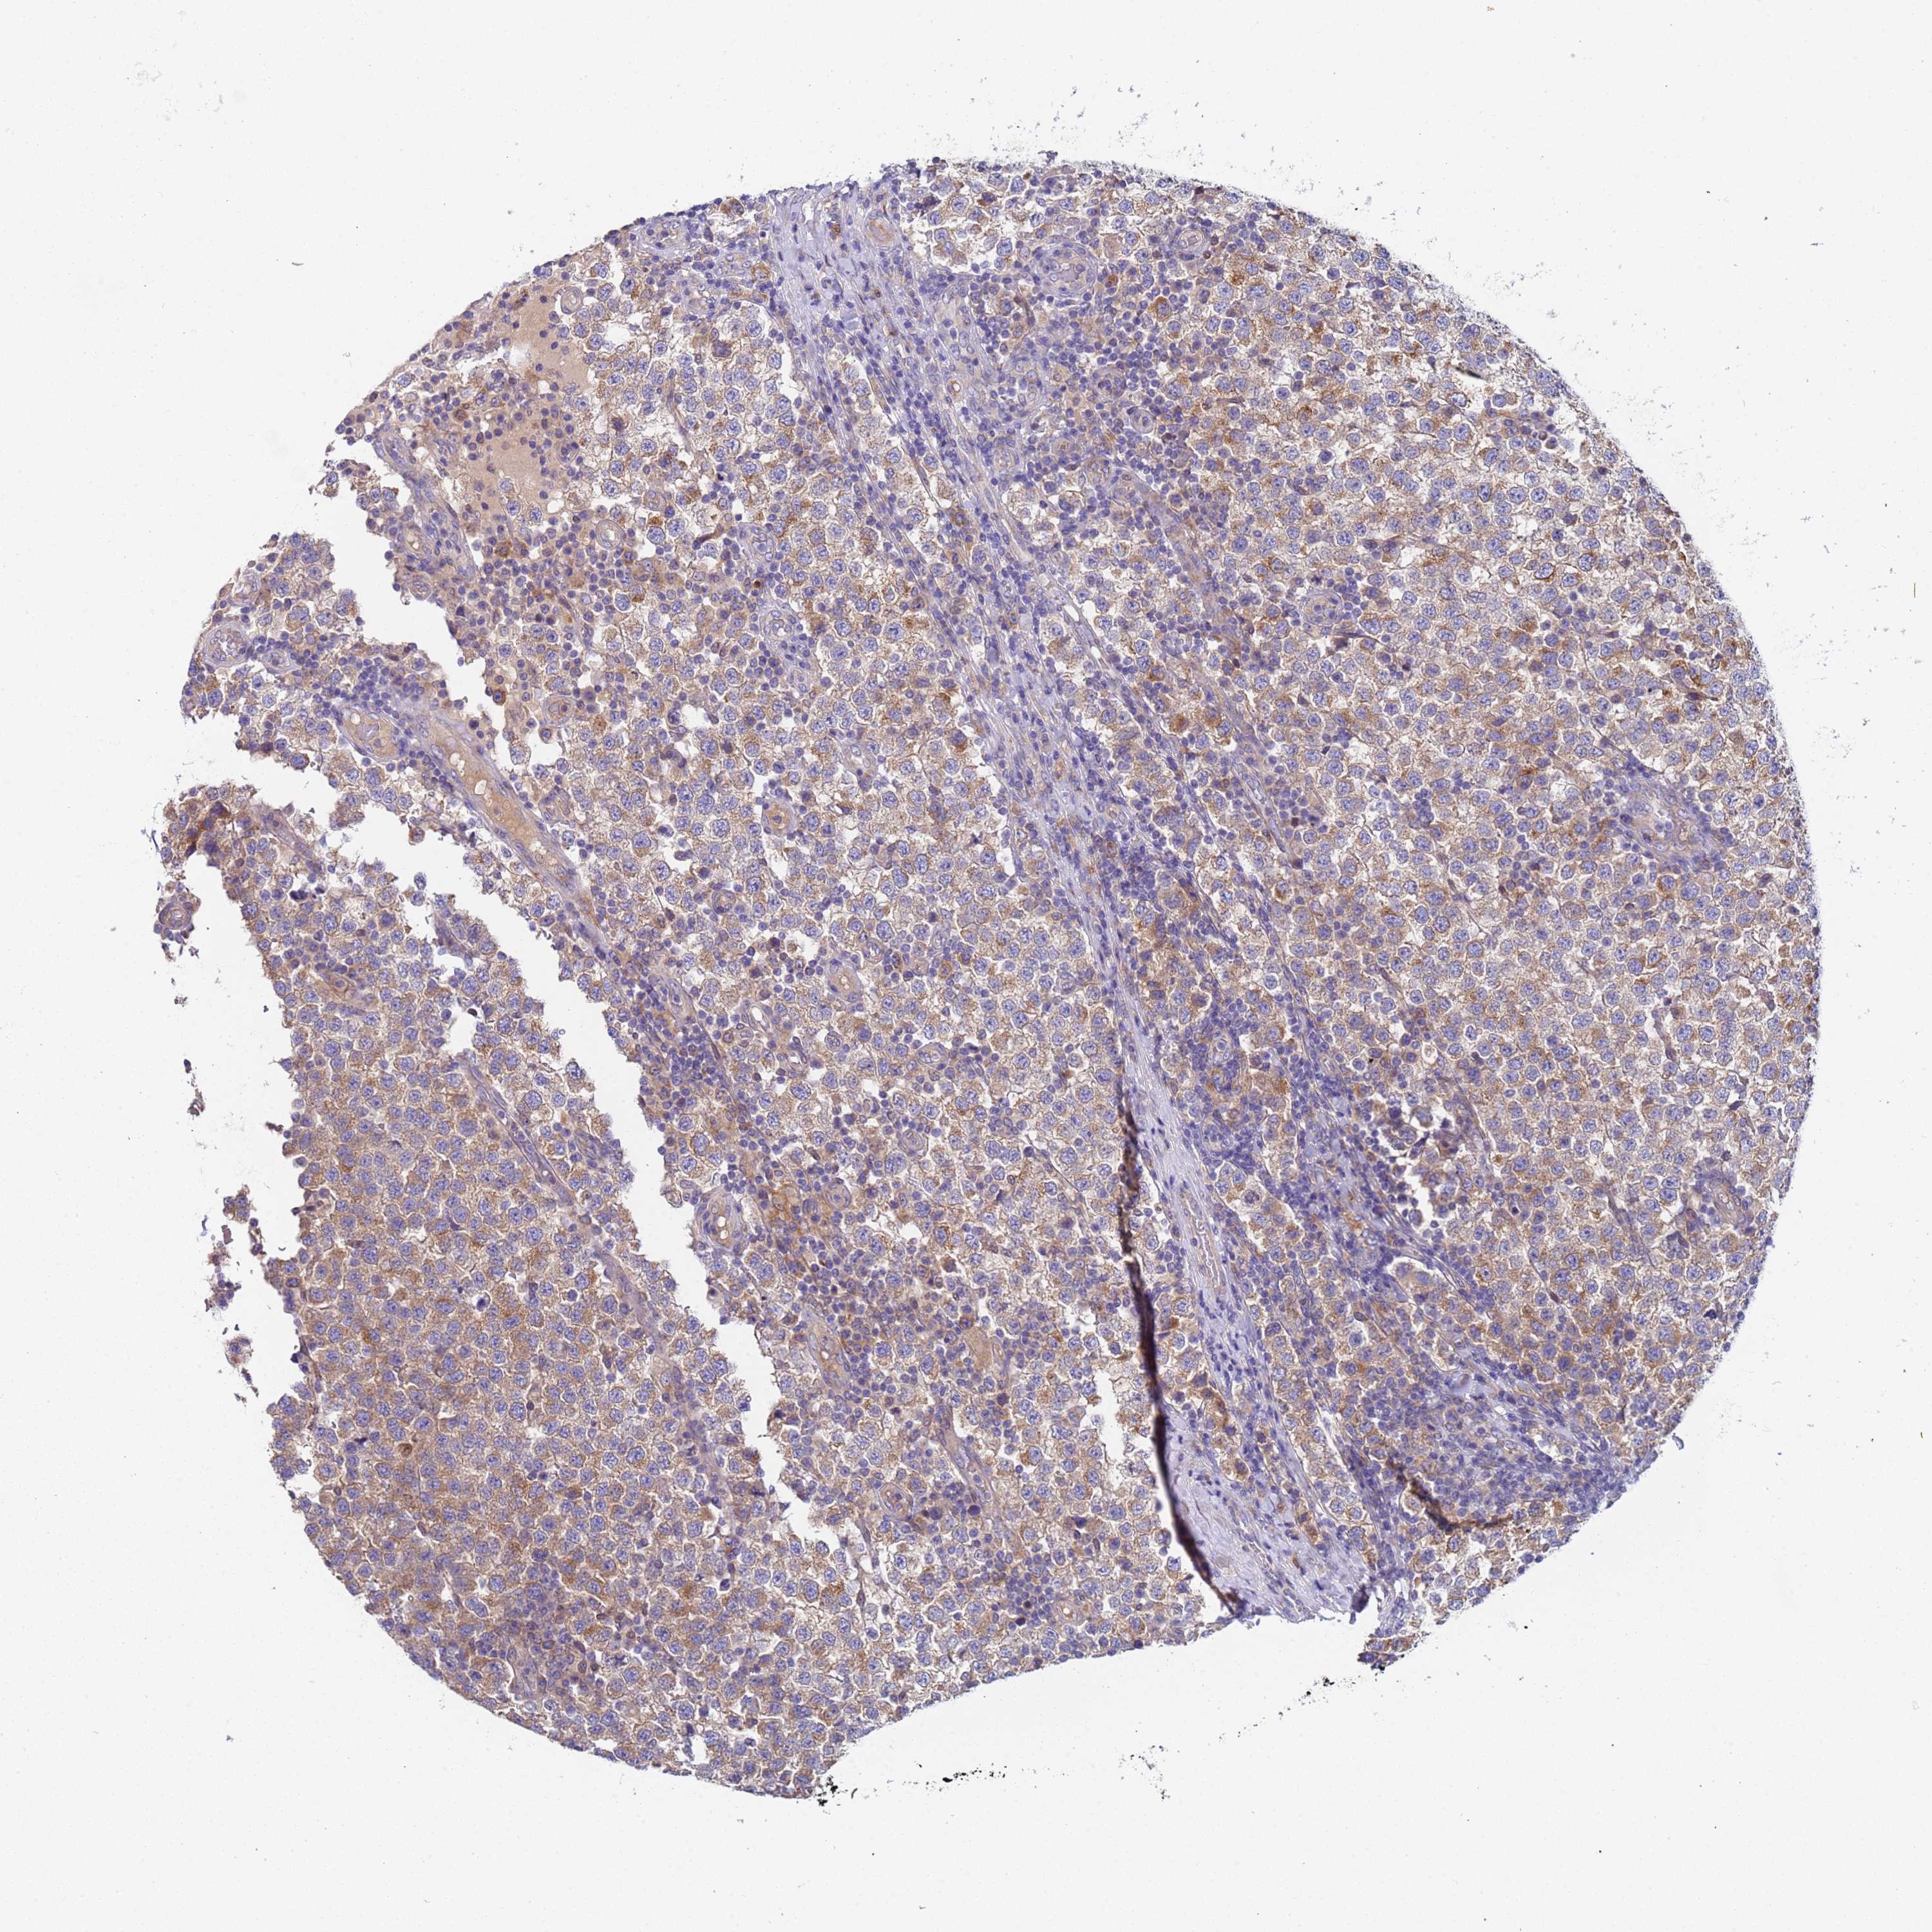

TESTIS CANCER - Protein expressioni

A mouse-over function shows sample information and annotation data. Click on an image to view it in a full screen mode. Samples can be filtered based on level of antibody staining by selecting one or several of the following categories: high, medium, low and not detected. The assay and annotation is described here.

Note that samples used for immunohistochemistry by the Human Protein Atlas do not correspond to samples in the TCGA dataset.

Antibody stainingi

Antibody staining in the annotated cell types in the current human tissue is reported as not detected, low, medium, or high, based on conventional immunohistochemistry profiling in selected tissues. This score is based on the combination of the staining intensity and fraction of stained cells.

Each image is clickable and will lead to virtual microscopy that enables deeper exploration of all samples and also displays staining intensity scores, fraction scores and subcellular localization as well as patient and tissue information for each sample.

Antibody HPA046936

Staining

High

Medium

Low

Not detected

Intensity

Strong

Moderate

Weak

Negative

Quantity

>75%

75%-25%

<25%

None

Location

Nuclear

Cytoplasmic/membranous

Cytoplasmic/membranous,nuclear

Carcinoma, Embryonal, NOS

Seminoma, NOS